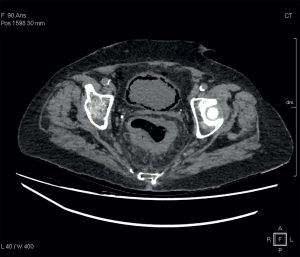

Un syndrome infectieux inexpliqué

Mme B., 90 ans, est adressée au service des urgences pour des douleurs lombaires et de l’épaule gauche, secondaires à des chutes. Ses antécédents médicaux se résument à un diabète…